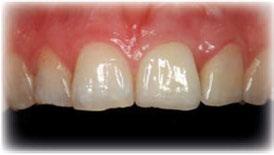

A las 24 horas se citó al paciente nuevamente, se atornilló el provisional en boca y se realizó una

Figura 24. Provisional finalizado tras acabado y pulido en el laboratorio.

Figura 25. Provisional finalizado tras acabado y pulido en el laboratorio.

Figura 26. Entrega del provisional de carga inmediata a las 24 horas.

Figura 27. Ortopantomografía del provisional atornillado en boca para verificar ajuste.

ortopantomografía de verificación del ajuste pasivo de todos los implantes. Por último, tapamos las chimeneas con teflón y resina provisional y se chequeó nuevamente la oclusión, dando nuevamente las instrucciones de higiene y mantenimiento de la prótesis provisional (Figuras 24-27).